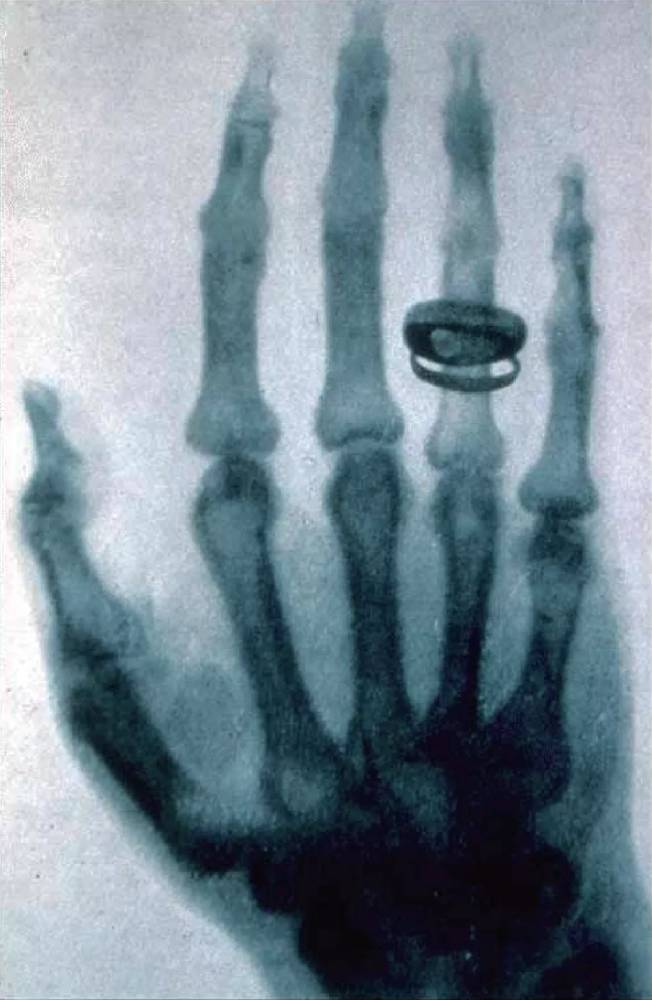

虽然很肯定自己发现了一种新射线 (或粒子流),但是伦琴心中还是非常焦虑忐忑,他深恐万一这些屏幕上的亮光只是因为长时间在暗室中工作,由于眼睛疲乏而造成的幻觉 (眼缬)。他担心倘使轻率发表了不真实的虚幻测量结果,岂不就声名扫地,学术生涯告终了。因此在反复自问与测试的过程中,他恍如失魂落魄,不与人交谈,并且禁止任何人进入实验室。直到12月22日,伦琴终于邀请他的太太到实验室,请她允许他用X光拍摄她的手,这就是科学史上著名的伦琴太太的手指头及结婚戒指X射线照片的由来。(在拍摄她太太的手之前,伦琴已经无意间发现了X光会穿透他自己的肌肤,但他一则不愿告诉别人,二则仍有些许担心这是来自眼睛疲劳所造成的幻觉。而当毫无心理准备,突然看到了自己的手骨头的照片之后,伦琴夫人似乎惊吓过度,从此拒绝再进入实验室。伦琴此时决定立即公开他的实验结果,他对着太太说“特大麻烦来了”(“Now the devil will be topay”)。)

图2 伦琴在演讲当场拍摄的著名解剖学家科力克的手的X射线照片,取自 X-ray|Psychology Wiki|Fandom (wikia.org)

在Würzburg Physical Medical Society的会议中,伦琴当场为出席演讲的当时著名的解剖学家科力克 (Albert von Kölliker) 拍摄了他的手,这张射线照片即使以100多年后的今天的标准来说,仍是影像清晰透彻的 (图2)。也是在这一场演讲中,Kölliker建议把X光命名为“伦琴射线”。